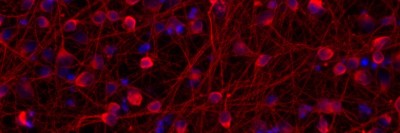

MSK Researchers Hack Neurons’ Internal Clocks To Accelerate the Study of Neurological Diseases

New research led by MSK has uncovered a way to “hack” neurons' internal clocks to speed up their development. The approach promises to accelerate research into neurological disease.

A 'Quick-and-Easy' Recipe for Making Brain Cells

Using stem cells, scientists can create batches of cortical neurons to study schizophrenia and autism.

Researchers Fast-Forward Stem Cell Aging to Study Degenerative Diseases

A team of Memorial Sloan Kettering scientists has come up with an approach to make stem-cell-derived neurons rapidly age in a cell culture dish. The breakthrough could transform research into Parkinson’s and other late-onset diseases.